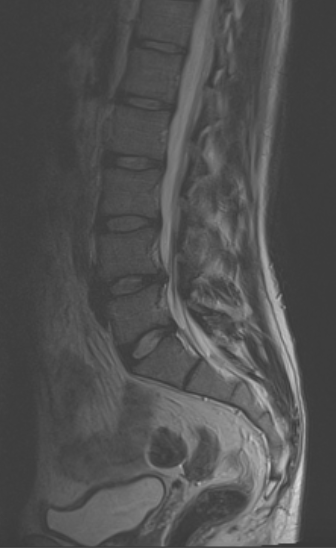

En el TLIF MIS (Transforaminal Lumbar Interbody Fusion Minimal Invasive Surgery) se obtiene el mismo resultado que el TLIF clásico o abierto, con la diferencia que sólo se realizan dos incisiones paramedianas y no se separa la musculatura de sus anclajes osteoligamentosos. El postoperatorio es mucho mejor en el TLIF MIS que en una cirugía abierta, sin embargo muchas veces no se puede plantear TLIF MIS y hay que realizar TLIF «abierto», sobre todo en patología degenerativa avanzada cuando vamos a asociarlo con otras técnicas (Laminectomía lumbar o artrectomía bilateral para corrección de lordosis o listesis).

-XLIF (DLIF, LLIF), OLIF: El uso de XLIF se ha generalizado para el tratamiento de la escoliosis degenerativa lumbar y la corrección del balance sagital. Los niveles donde más suele emplearse son L2-L3 y L3-L4. El abordaje mínimamente invasivo en un flanco lateral del abdomen permite acceder al disco desde el espacio retroperitoneal, realizando una pequeña incisión en el psoas. La colocación de una prótesis de gran tamaño (comparada con otras técnicas como PLIF o TLIF) que ocupa todo el diámetro coronal de la vértebra permite una corrección del espacio intervertebral, recuperando la altura del disco originaria y la lordosis, lo que provoca una descompresión posterior indirecta sobre el ligamento amarillo al tensarlo de nuevo.

La escoliosis degenerativa requiere a menudo de abordajes extensos para fusionar muchos niveles. El postoperatorio de estos pacientes es arduo y no exento de complicaciones. La técnica de XLIF (OLIF) aplicada en esta patología en dos o tres niveles permite una fusión adecuada que puede combinarse con una instrumentación posterior percutánea +/- una descompresión selectiva microscópica a través de pequeñas incisiones con poca pérdida de sangre y escaso daño a la musculatura posterior.